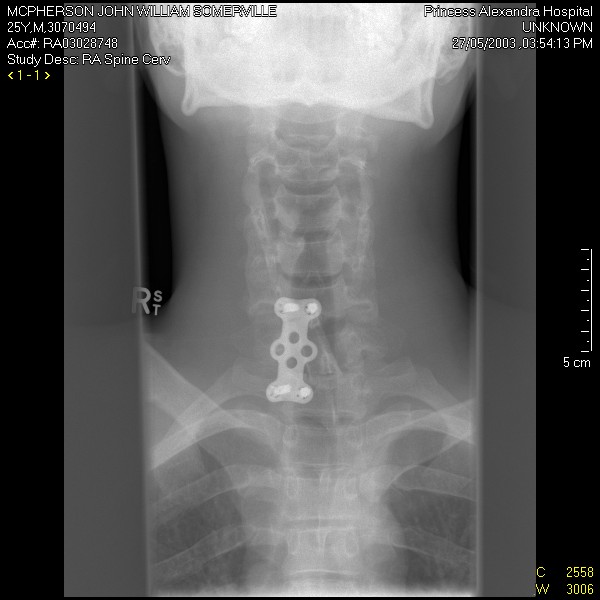

Also, I compression fractured T6-T9(broken back) so, I would never wear anything that put any pressure in the center of my back/loading my spine! I don't ride anymore though so, moot point!

Compression fractures of the Thoracic spine are caused by hyperflexion. The rear strut of the neck brace is not loaded during hyperflexion.

I understand that Cam, we'll just call it post accident "phobia"!!!

If it was designed to protect your thoracic spine it would extend all the way down your back. It is designed to protect the most vulnerable part of your spine. Your neck.